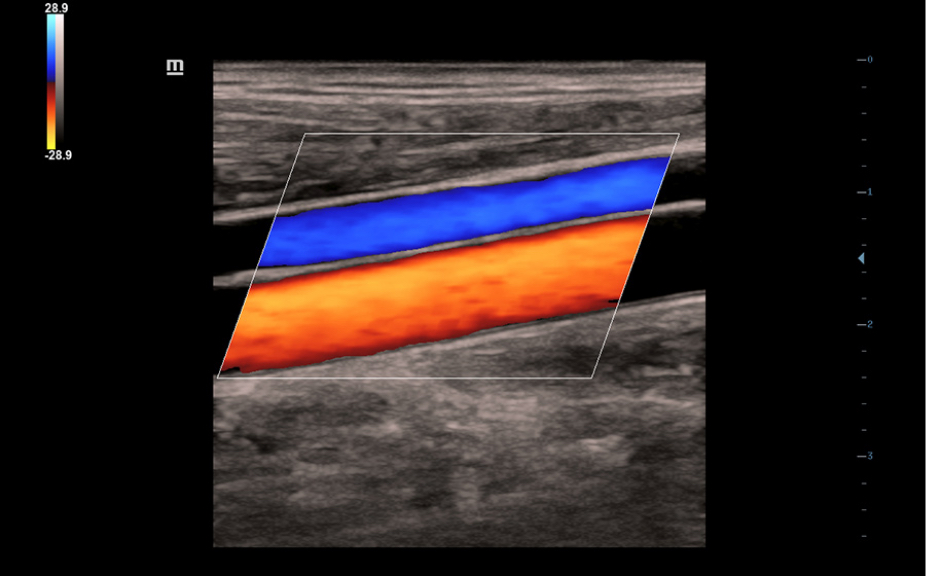

?ematik ve ultrason resimleri dahil, normal anatomik g?sterimler.

Standart ultrasonogram?n, ilgilenilen b?lge ĂŒzerinde g?rsel rehberlik sa?layan yan

g?rĂŒnĂŒmĂŒ.

Standart ultrason g?rĂŒntĂŒleri

3

Referans i?in ger?ek zamanl? tarama kar??la?t?rmas?.